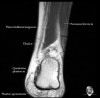

- Axial section

Axial PD fat suppression evaluates the tendons and ligaments of the ankle particularly after acute/subacute injuries. It also is sensitive to talar dome osteochondral defects. Alternatively, a T2 sequence can be used to eliminate magic angle artifact that may occur as the tendons travel around the malleolar turns.

Tibiofibular ligaments

Lateral ankle ligaments

Deltoid and spling ligaments

Tendon(Achilles, Medial, Lateral, Anterior)